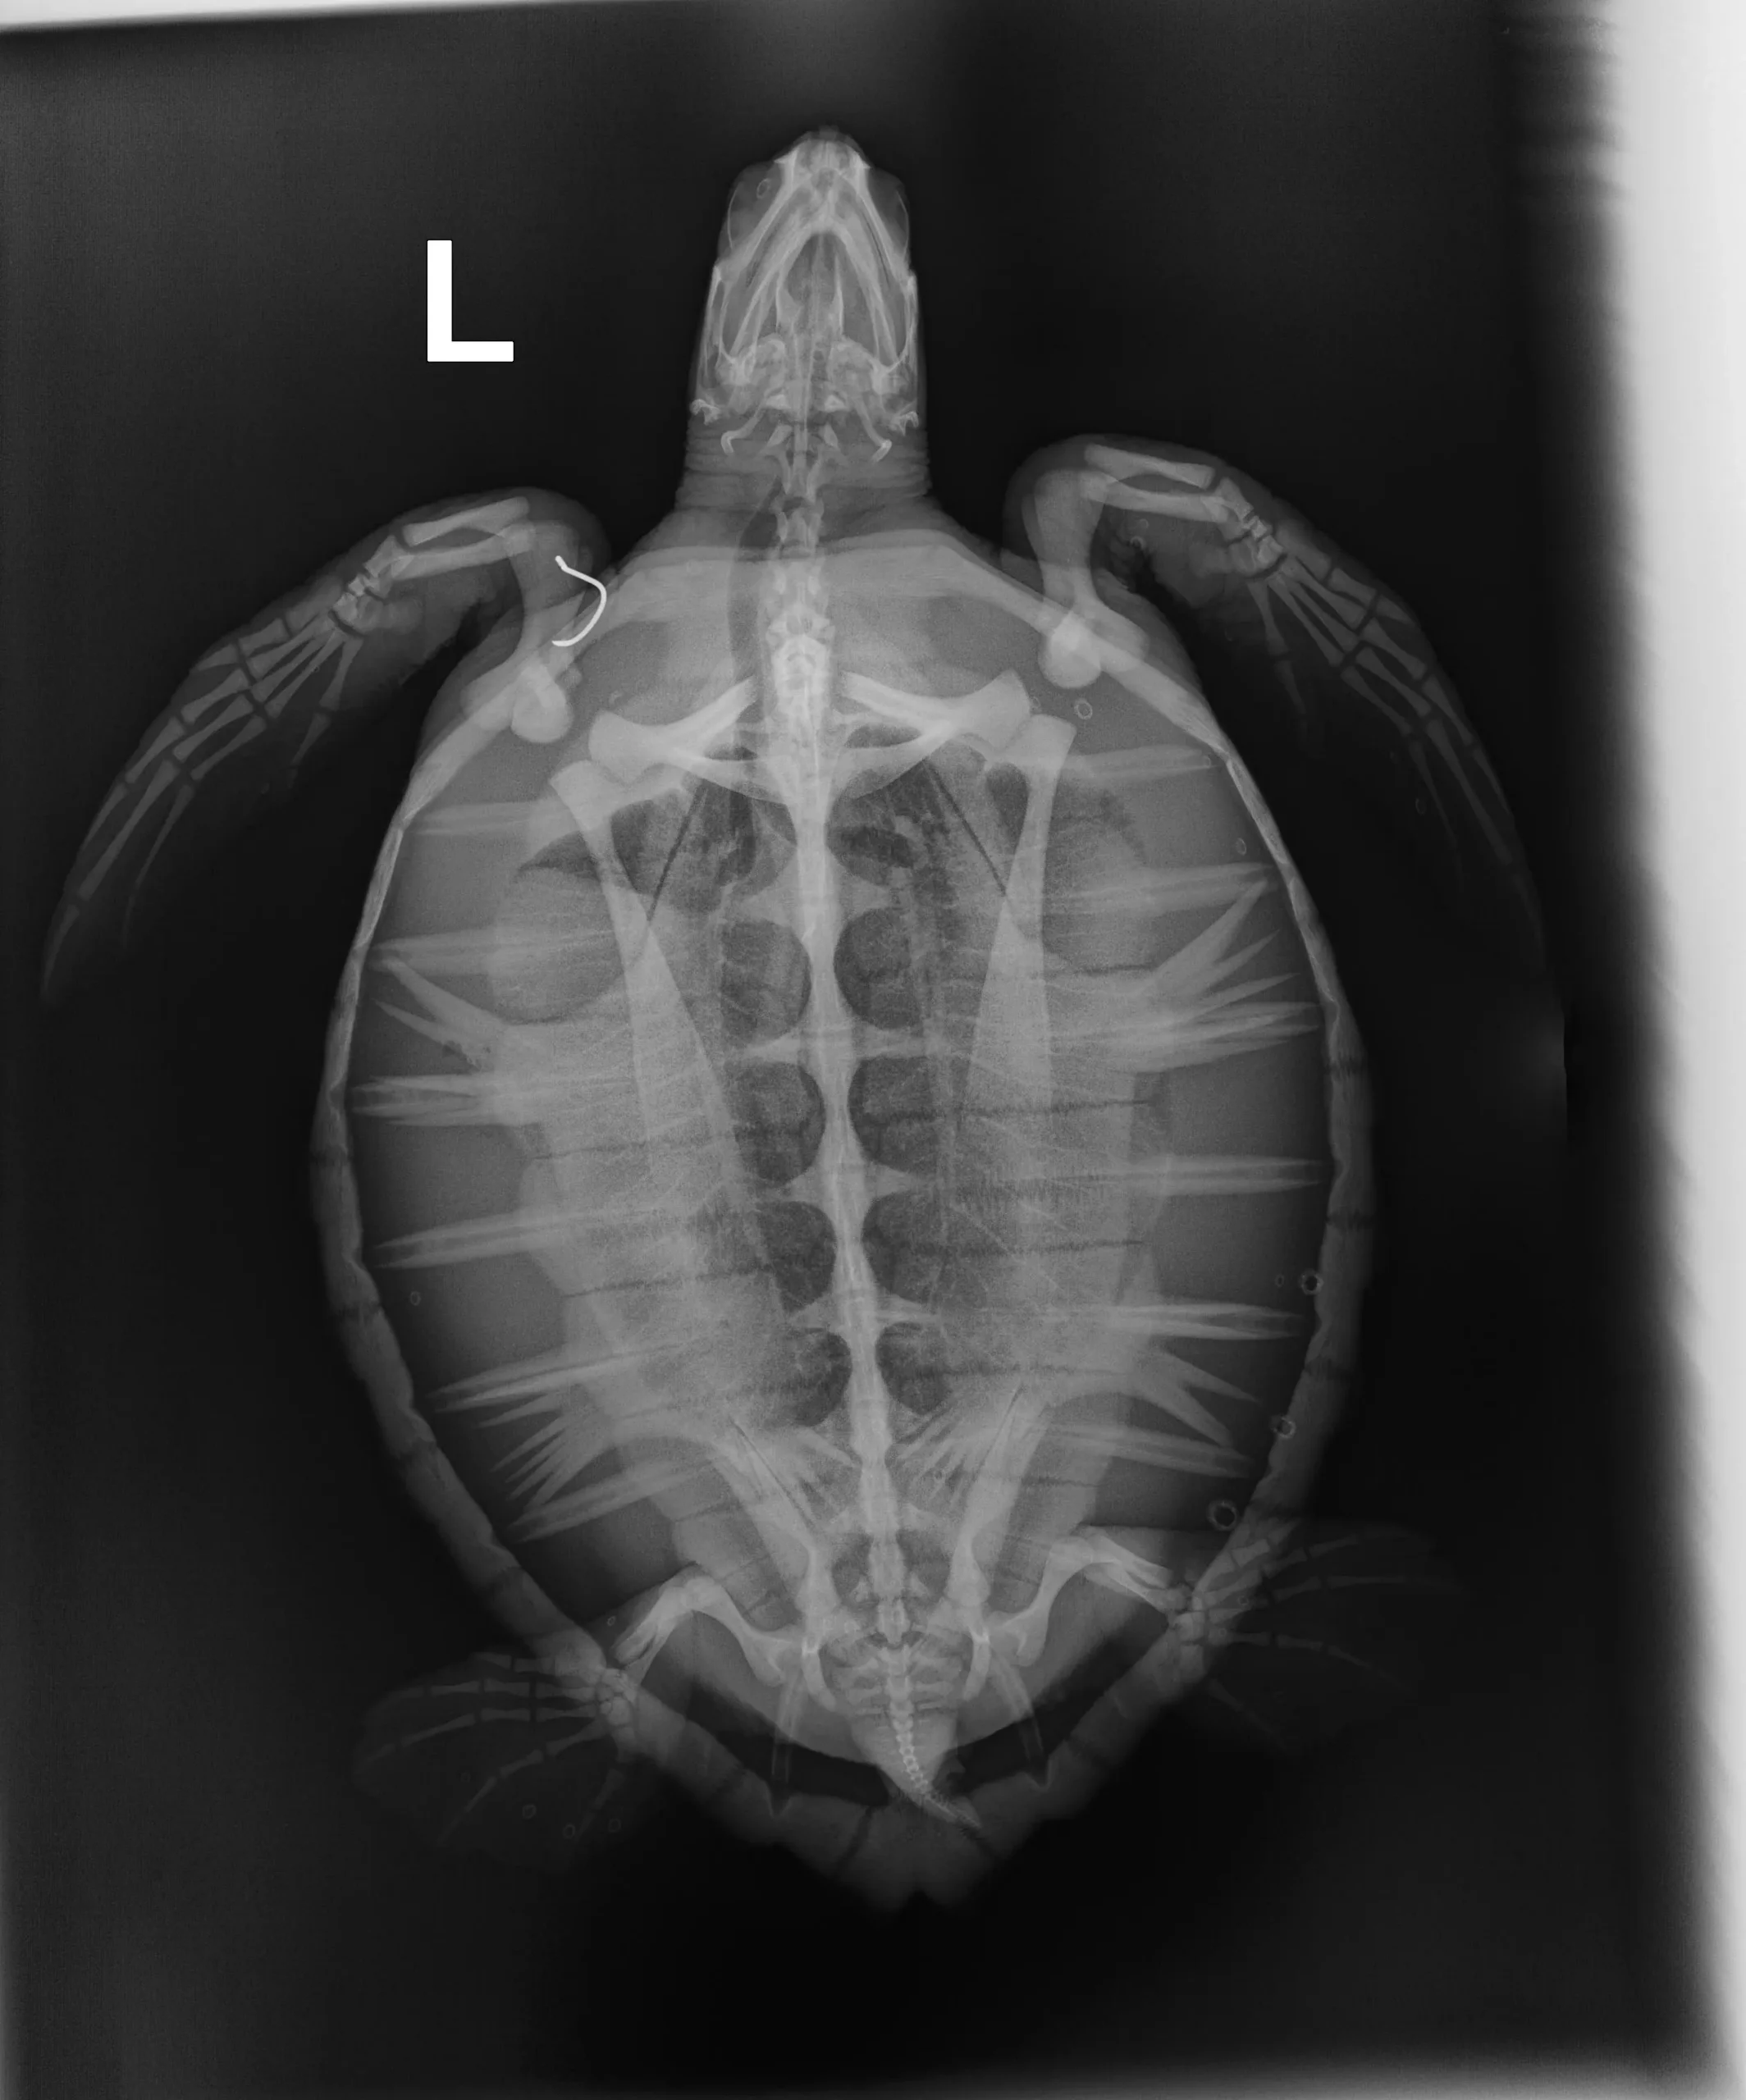

2.50 kg/5.00 lbs juvenile Atlantic Green sea turtle

Plastron (belly): Urchin spines and some small abrasions

External Wounds: Hook in left shoulder

Head/Flippers/Soft Tissue: Notch missing out of trailing edge of the right flipper